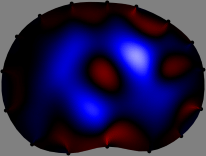

Refer to caption

Figure 2: Fidelity-embedded regularization method. (Left bottom) Correlations between four different column vectors (𝐒ksubscript𝐒𝑘{\bf S}_{k}) and all the remaining column vectors (𝐒subscript𝐒{\bf S}_{\ell}) are visualized. (Right bottom) Performances of the proposed fidelity-embedded regularization method for λ=𝜆\lambda=\infty are shown by numerical simulations.

To explain the FER method, we closely examine the correlations among column vectors of the sensitivity matrix 𝕊𝕊\mathbb{S}, described in Fig. 2. The correlation between 𝐒ksubscript𝐒𝑘{\bf S}_{k} and 𝐒subscript𝐒{\bf S}_{\ell} can be expressed as

for i=1,,16𝑖116i=1,\cdots,16[23]. This shows that the column vector 𝐒ksubscript𝐒𝑘{\bf S}_{k} is like an EEG (electroencephalography) data induced by dipole sources with directions uj,j=1,,16formulae-sequencesubscript𝑢𝑗𝑗116\nabla u_{j},j=1,\cdots,16 at locations ΔksubscriptΔ𝑘\Delta_{k}. Given that two dipole sources at distant locations produce mutually independent data, the correlation between 𝐒ksubscript𝐒𝑘\mathbf{S}_{k} and 𝐒subscript𝐒\mathbf{S}_{\ell} decreases with the distance between ΔksubscriptΔ𝑘\Delta_{k} and ΔsubscriptΔ\Delta_{\ell}. Fig. 2 shows a few images of the correlation 𝐒k,𝐒(|𝐒k||𝐒|)1subscript𝐒𝑘subscript𝐒superscriptsubscript𝐒𝑘subscript𝐒1\left\langle\mathbf{S}_{k},\mathbf{S}_{\ell}\right\rangle(|\mathbf{S}_{k}||\mathbf{S}_{\ell}|)^{-1} as a function of \ell for four different positions ΔksubscriptΔ𝑘\Delta_{k}. The correlation decreases rapidly as the distance increases. In the green regions where the correlation is almost zero, 𝐒subscript𝐒{\bf S}_{\ell} is nearly orthogonal to 𝐒ksubscript𝐒𝑘{\bf S}_{k}.

Fig. 2 shows that if ΔksubscriptΔ𝑘\Delta_{k} and ΔsubscriptΔ\Delta_{\ell} are far from each other, the corresponding columns of the sensitivity matrix are nearly orthogonal. This somewhat orthogonal structure of the sensitivity matrix motivates an algebraic formula that directly computes the local ensemble average of conductivity changes at each point using the inner product between changes in the data and a scaled sensitivity vector at that point: